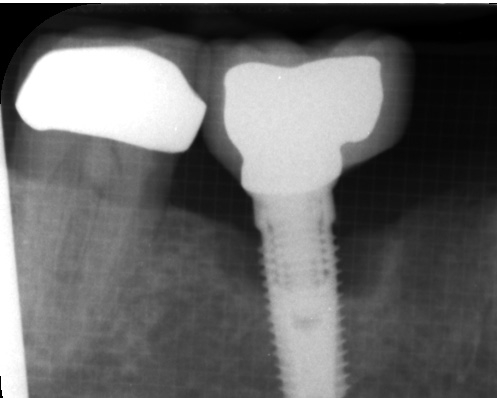

Wissenschaftliche Untersuchungen nehmen allerdings nun immer mehr die besonderen Eigenschaften des Implantatmaterials und seiner Oberflächenmorphologie in die Betrachtung. Als ein sehr oxidationsfreudiges Metall bildet Titan im physiologischen Milieu Oxidschichten auf seiner Oberfläche aus, die zur Passivierung führen und vor Korrosion schützen [17]. Einerseits fördert die Rauigkeit der Oberfläche die Osseointegration, anderseits begünstigt sie aber auch einen Partikelabrieb [18]. Seit zwei Jahrzehnten ist der wissenschaftliche Fokus auf die Auswirkungen von Titanpartikeln gelenkt, die sich durch mechanischen Abrieb beim Einbringen und durch korrosive Ereignisse (Bio-Tribocorrosion) von der Implantatoberfläche ablösen und als Mikro- und Nanopartikel immunologische Effekte im Organismus verursachen [19,20]. Titanoxidpartikel zeigen im Vergleich mit anderen Oxidpartikeln aus Aluminium- oder Zirkonkeramik eine deutlich höhere immunstimulative Potenz [21]. Makrophagen reagieren nach Kontakt mit Titanoxidpartikeln mit einer Ausschüttung der proentzündlichen Zytokine TNF-? und IL-1, was u.a. analog zur Pathogenese der Parodontitis eine Osteoklastenaktivierung und damit einhergehend eine Osteolyse zur Folge hat [22].

Korrosionsfördernde Faktoren sind mechanischer, chemischer und elektrolytischer Natur (Tribokorrosion). Bereits die mechanische Reibung beim Inserieren eines Implantates als auch Mikrobewegungen bei der Belastung führen zum Partikelabrieb, der im Nanometerbereich liegenden dünnen Oxidschicht am Implantat-Knochen-Interface und am Implantat-Abutment-Interface [23-25]. Im Vergleich von Implantatsystemen mit und ohne „platform-switching“ zeigten die letzteren eine höhere Partikelbeladung im periimplantären Gewebe. Die Ausprägung der ausgeschütteten Zytokin-Spiegel war proportional zur Gewebepartikellast. In radiologischen Kontrolluntersuchungen erwies sich deshalb das crestale Knochenniveau um Implantate mit „platform-switching“ im Verlauf als stabiler [26]. Erhöhte Partikelbeladung des Implantat umgebenden Gewebes findet sich auch nach Scaling-Maßnahmen an der Implantatoberfläche [27]. Die genannten Faktoren führen alle zu einer Partikeldissemination in umliegende und auf dem Blut- und Lymphweg in entferntere Gewebe und Organe. Mechanischer Abrieb und korrosive Prozesse verstärken sich dabei gegenseitig. Mit der elektronenmikroskopischen Spektroskopie (scanning electron microscopy-energy dispersive spectroscopy, SEM-EDS) gelang der Nachweis von Titannanopartikeln (NP) im periimplantären Knochen von Minischweinen. Der Vergleich verschiedener Implantatoberflächen ergab eine unterschiedliche Gewebebelastung in Abhängigkeit von Merkmalen wie Rauigkeit und mechanischer Verbundstabilität der aufgebrachten Oberfläche. Bereits am Tag nach der Implantatinsertion in den Kieferknochen der Versuchstiere waren Partikel im periimplantären Gewebe nachweisbar. Die Autoren schlussfolgern, dass mit der Zeit eine kritische Partikelbeladung im periimplantären Gewebe erfolgen könne, die eine Schädigung der Osteoblasten zur Folge habe [28].

Dr. Jacobi-Gresser